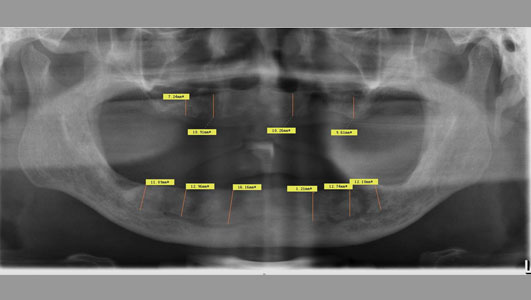

口腔全景图

通过三维数字口腔CT检查,电脑模拟和快速成型模型,王医生为他设计了一个最简单最舒适的种植方案:ALL-ON-4 即刻种植技术,无需植骨、无需戴牙等待,通过在上、下半口各植入4颗人工牙根,即可完成全口牙齿的重建。在牙根安装完后,下午医生即为李叔叔安装临时牙,整个治疗过程,仅需1-2个小时,且全程电脑操作,几乎没有肿痛。